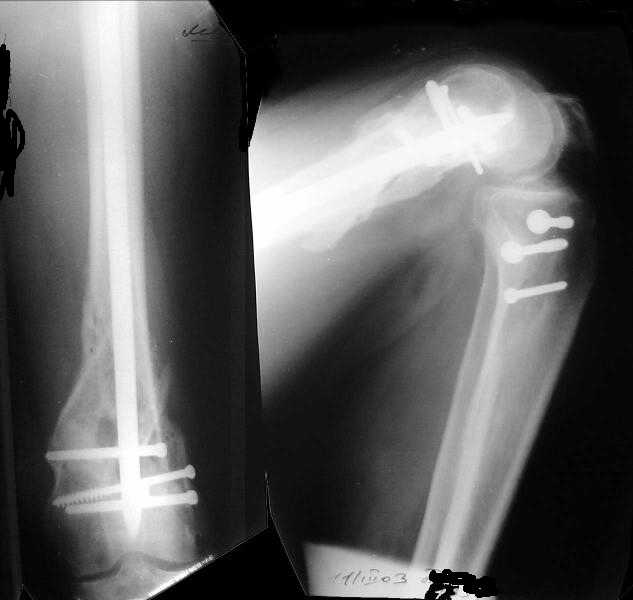

1

2

The mobilisation of knee is started immediately from the second day. Weight bearing is permitted as in any other interlocked nailing. That is, Toe touch to start with and within four days, partial to in another two weeks, full weight bearing. Of course that is assuming that the correct size nail has been used. Up to 70 kg body weight, 11no will be good enough and 12mm if more.Usually at the 1st followup, at 6 weeks time, they have full flexion..I

Enclosing a recent intraop picture